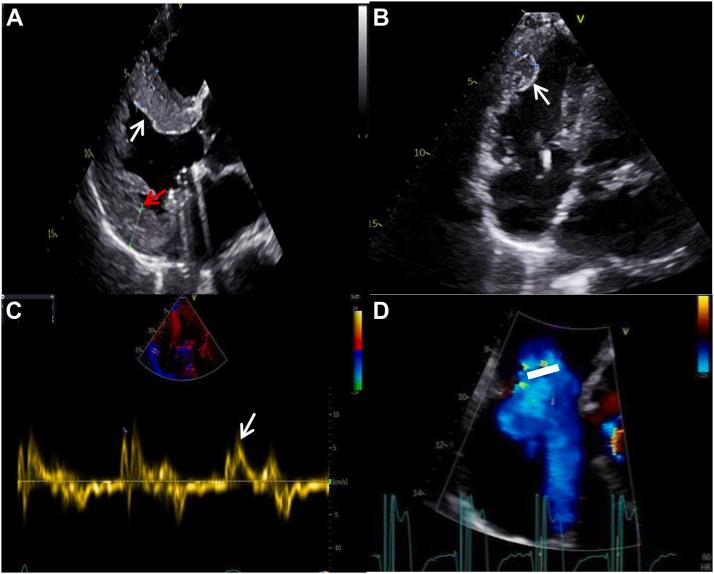

经导管三尖瓣置换术治疗伴有严重三尖瓣反流的安德森法布里病

Transcatheter Tricuspid Valve Replacement for Anderson Fabry Disease With Severe Tricuspid Regurgitation.

• Two-dimensional STE is useful for AFD diagnosis. • Increased LV wall thickness and multiorgan involvement should trigger suspicion of AFD. • Severe TR is rare for AFD. • TTVR is a novel therapy for AFD with severe TR.

摘要